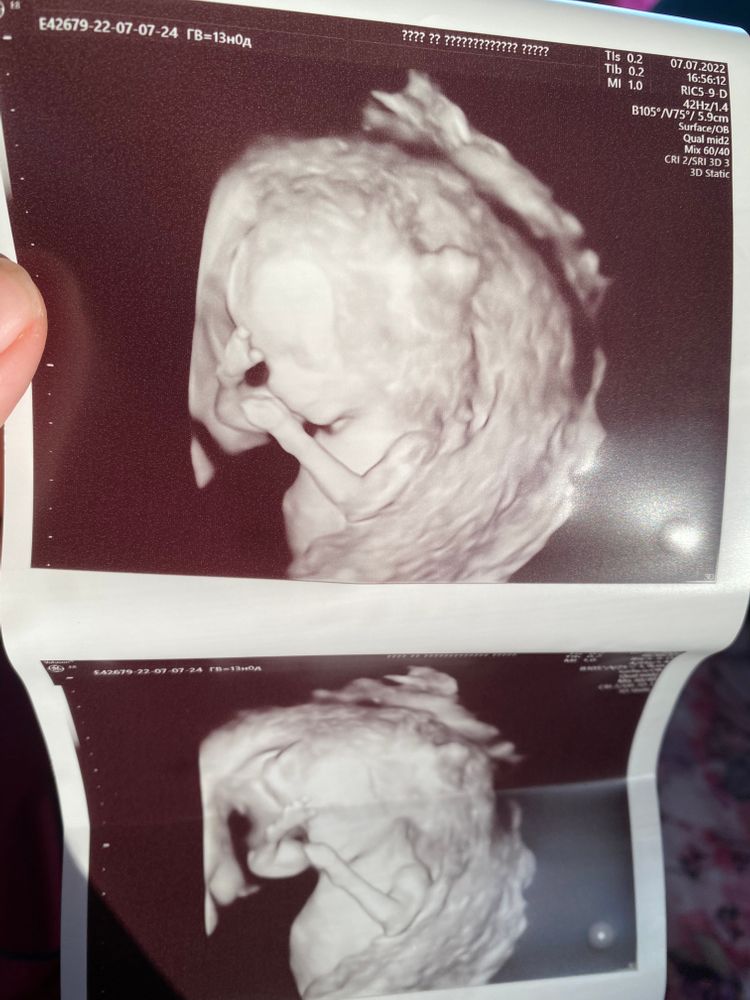

Фотка с первого скрининга)